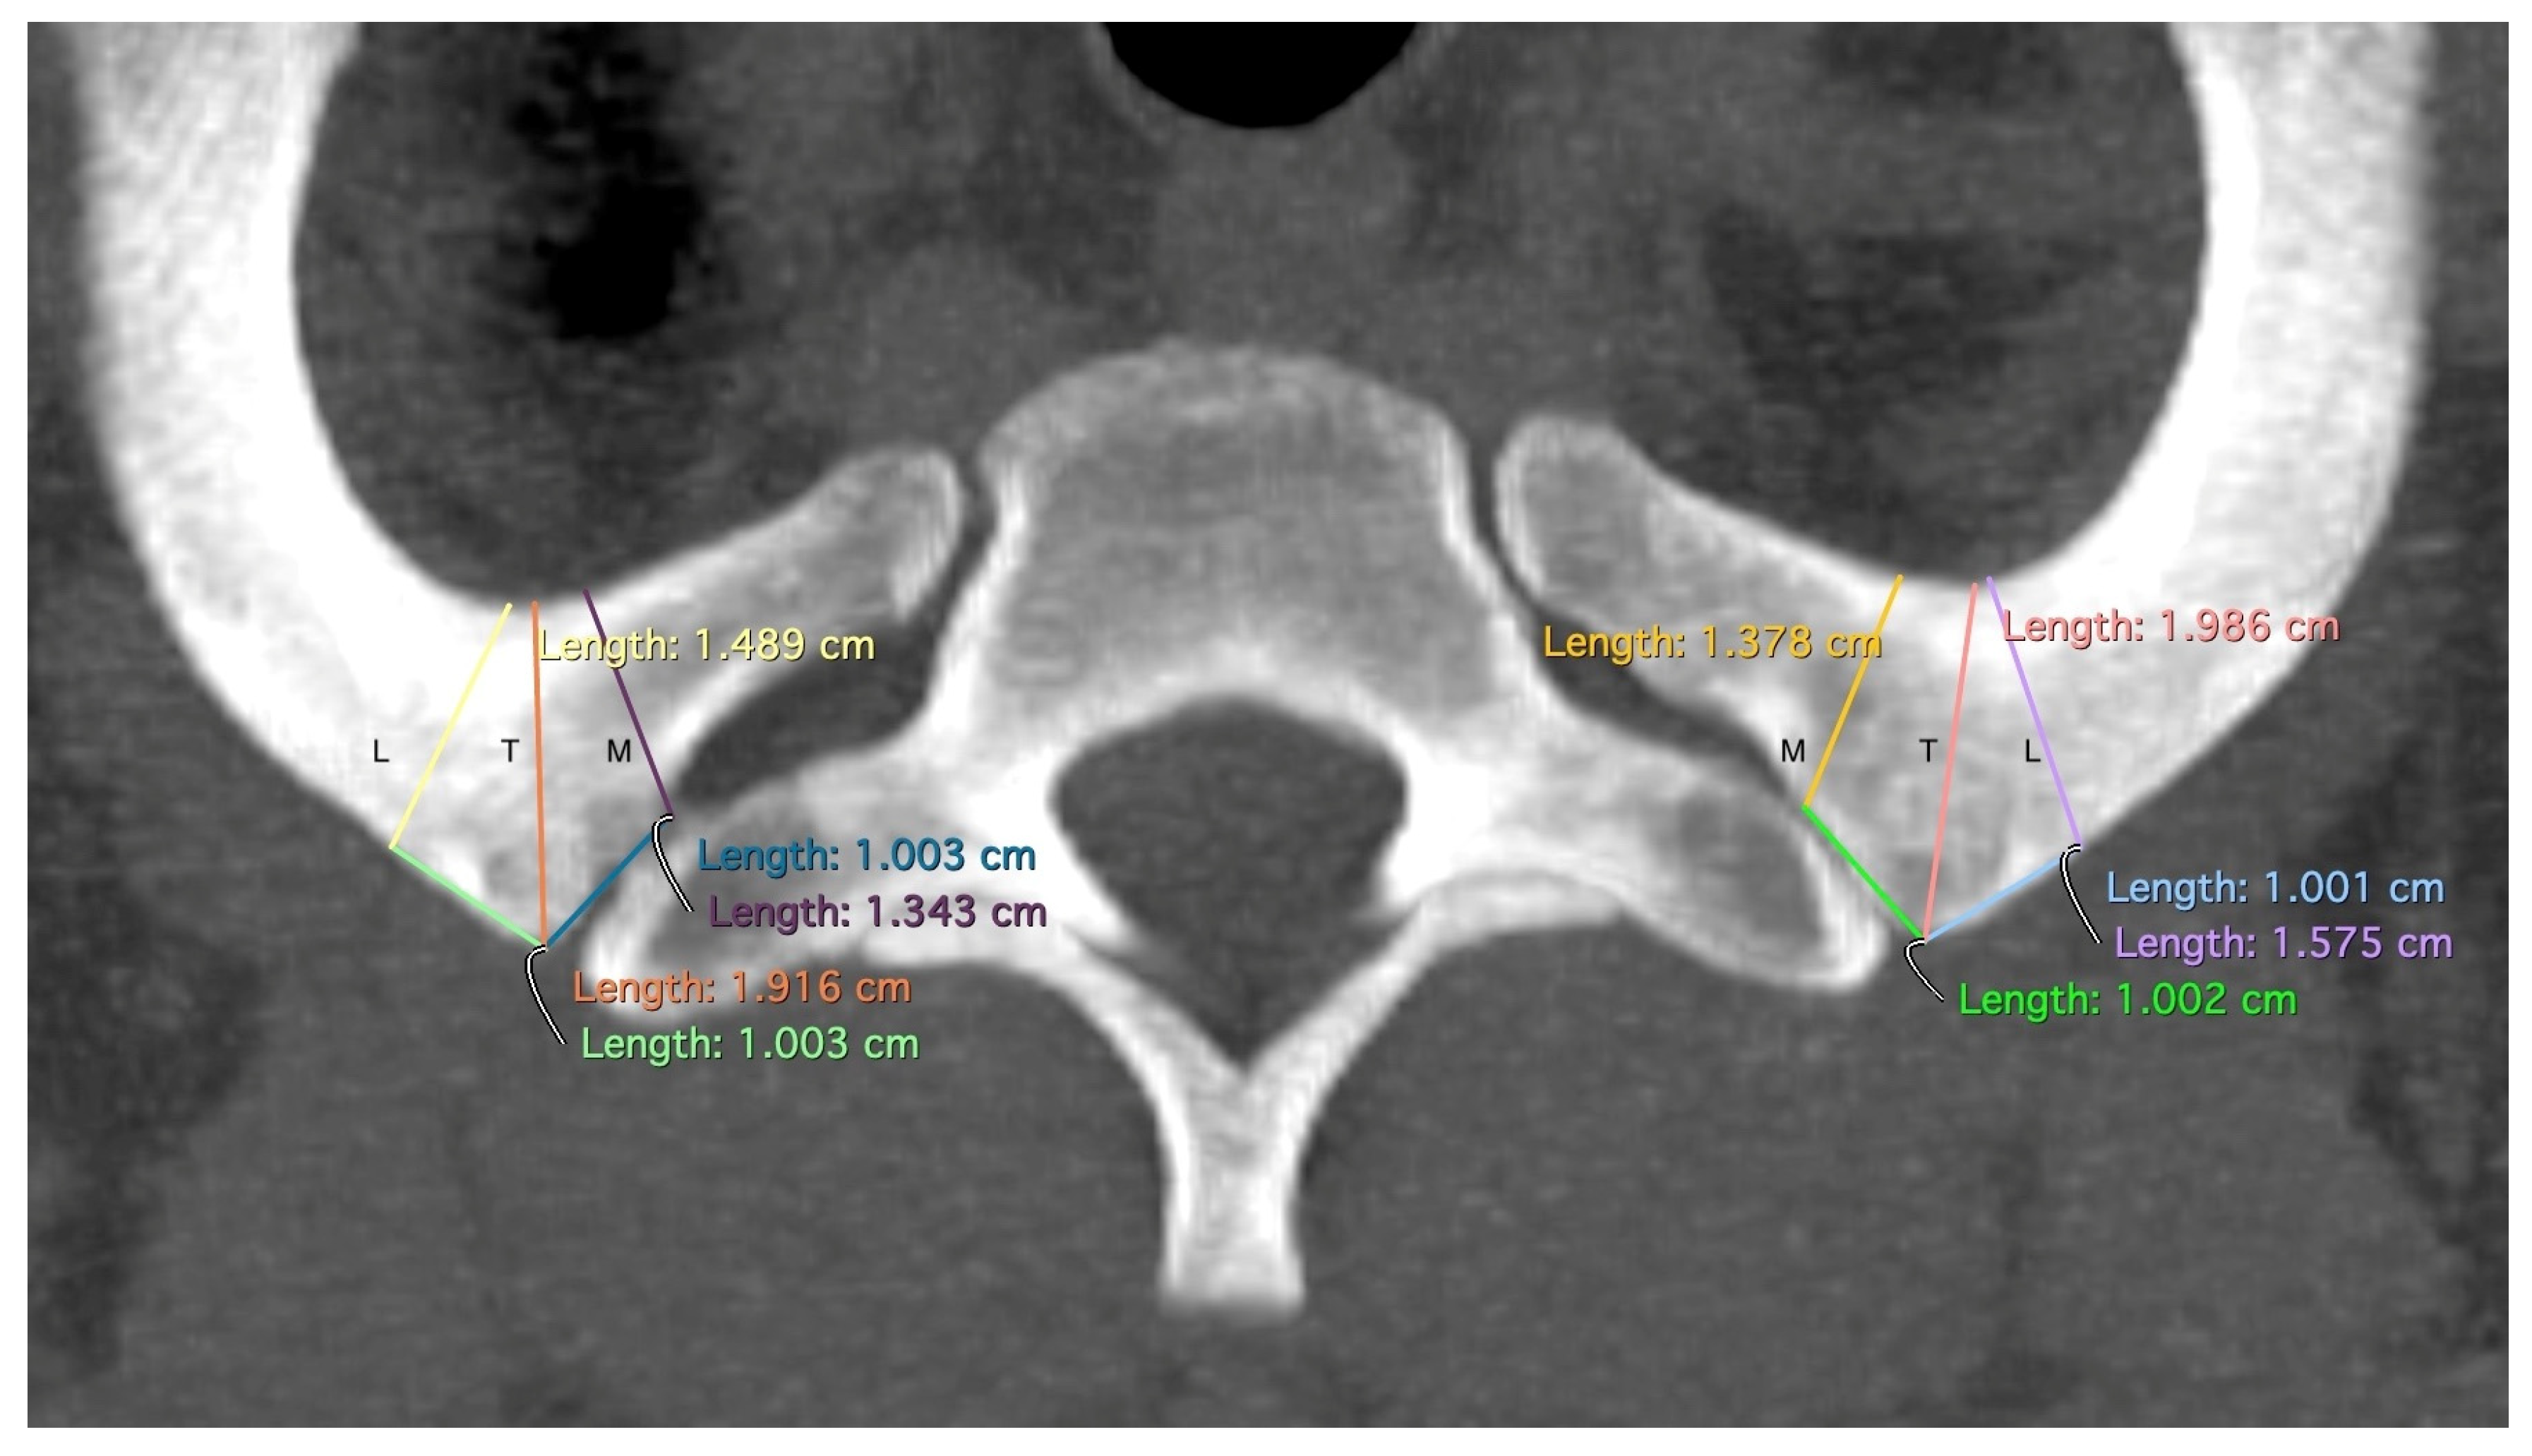

The “T”, “M”, and “L” distances specifically measure the area of the first rib that remains when TOD surgery is performed conventionally and that may be responsible for recurrences (Figure 2). The point at which the width of the rib is measured—at the level of the anterior edge of the first thoracic vertebra—has been shown in our dissection of body donors to be the point at which the Th1 root passes over the first rib with direct contact to the rib (Figure 3). The RAP distance measures the proximal extension of the first rib and its relationship to the first thoracic vertebral body (Figure 4).

Figure 2.

Measurement of T: the minimal width of the rib at the level of the tuberculum costae 1, M: the minimal width of the rib 1 cm medial to the tuberculum costae 1, and L: the minimal width of the rib 1 cm lateral to the tuberculum costae 1. Differently colored lines for better differentiation.